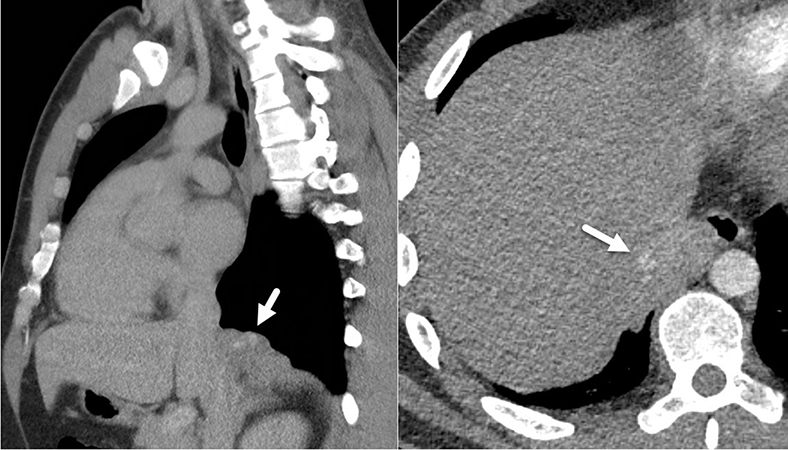

Clinical History: A 23-year-old man underwent a CT scan as part of the diagnostic workup following a hockey injury, presenting with dyspnea after the trauma. The scan revealed multiple thoracic nodules localized to the pleura, with the largest measuring 6,4 x 2,7 x 4,4 cm, located at the right lower lobe and extending towards mediastinum. Additional nodules were identified at the diaphragm and middle lobe. The clinical differential diagnosis included paraganglioma, neurofibroma, or possibly CPAM. Due to unsuccessful endoscopic FNAs, thoracoscopic surgery was performed with resection of the largest nodule. Intraoperatively, the nodule presented as a firm tumor measuring approximately 6 cm.

The CT-scan (Figure 1), macroscopic picture (Figure 2), representative histological images (Figures 3-5) and immunohistochemical stains (STAT6) are provided (Figure 6).